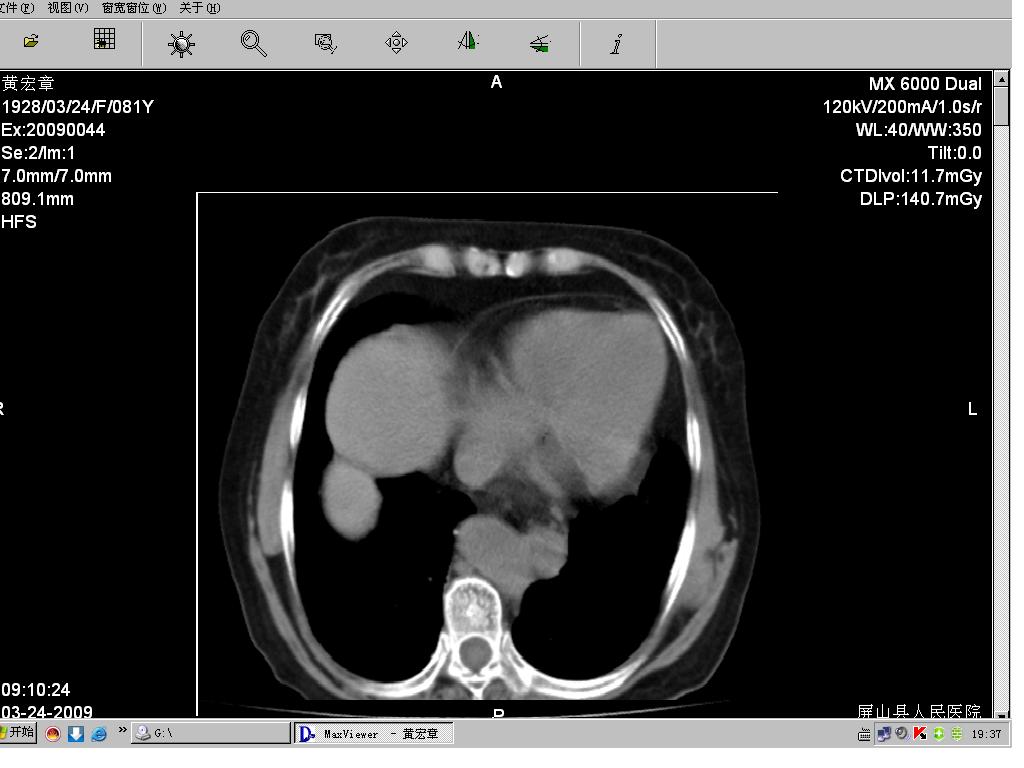

病人女,81岁,临床以呕血为主诉!请大家帮忙分析!

请问食管下段有问题没?

食道下端管壁好像是有点增厚,建议楼主查个钡餐排除一下食管裂孔疝的可能